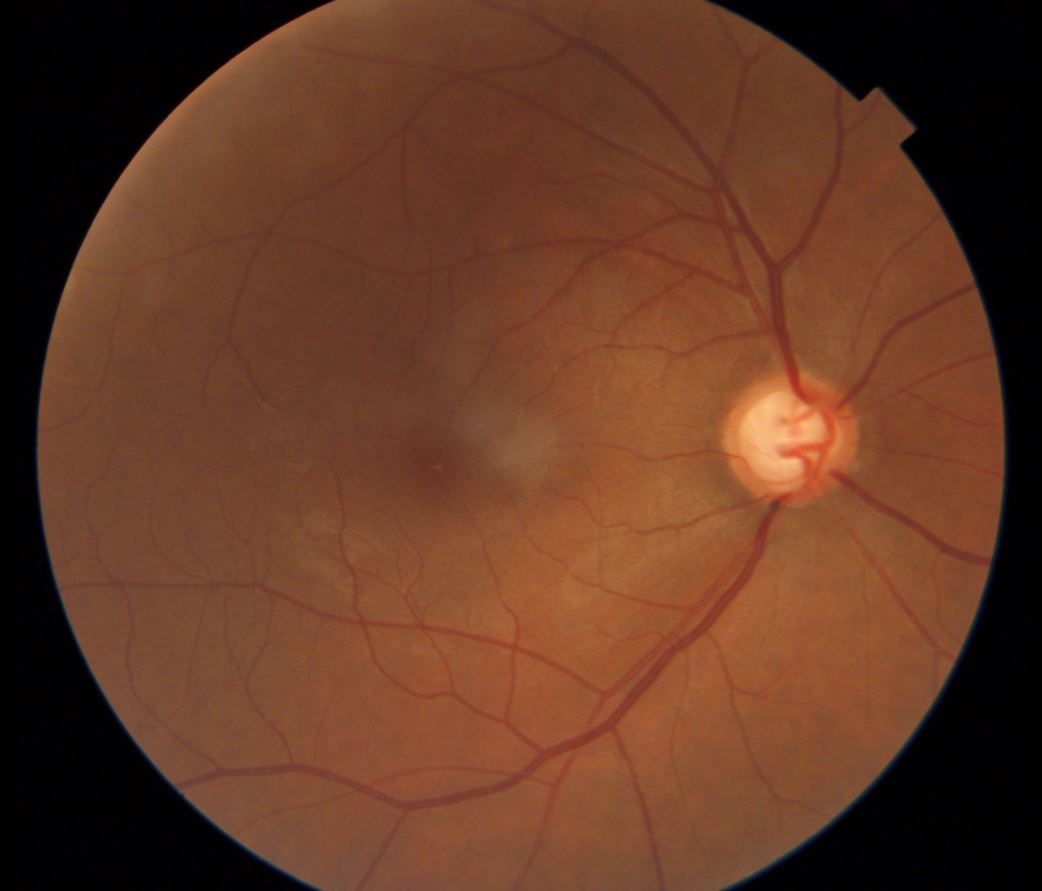

Technology is rapidly changing the eye care industry. We now have access to an amazing array of instruments which allow us to perform advanced testing and see layers of the retina in-situ.

At Eyedeal Optometrist we are proud to provide our patients with the latest technologies for earlier detection of eye diseases.

Macular degeneration (AMD) is a disease that affects the central vision of people over 50 years of age. It is the leading cause of visual impairment in Australia.

Diabetes can affect the small blood vessels at the back of the eye, leading to bleeding and scarring in the retina and possible irreversible vision loss.